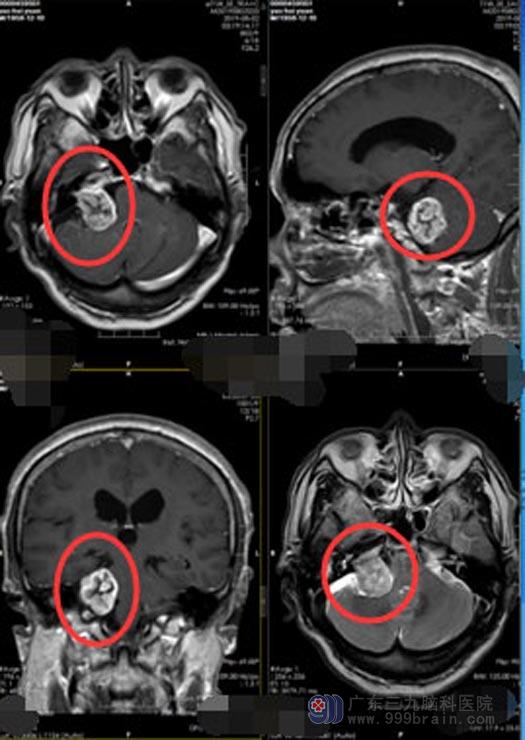

经过多方面的挑选,姚大爷终于来到了广东三九脑科医院神经外五科。进一步头颅MR检查,结果提示:右侧小脑角占位,考虑听神经鞘瘤,肿瘤大小有34mm×32mm×23mm。

在充分的检查与准备后,鲁明副院长主刀为姚大爷行“右侧桥小脑角区听神经鞘瘤切除术”。术中可见肿瘤上至三叉神经,下达末组颅神经,与面、听神经、脑干明显粘黏,周边临近重要血管,手术的难度极大。通过手术导航,精准定位肿瘤位置,显微镜下细心地分块完整地切除了肿瘤,同时保护了重要的血管与神经,免其受损伤。历时7小时,手术顺利完成。